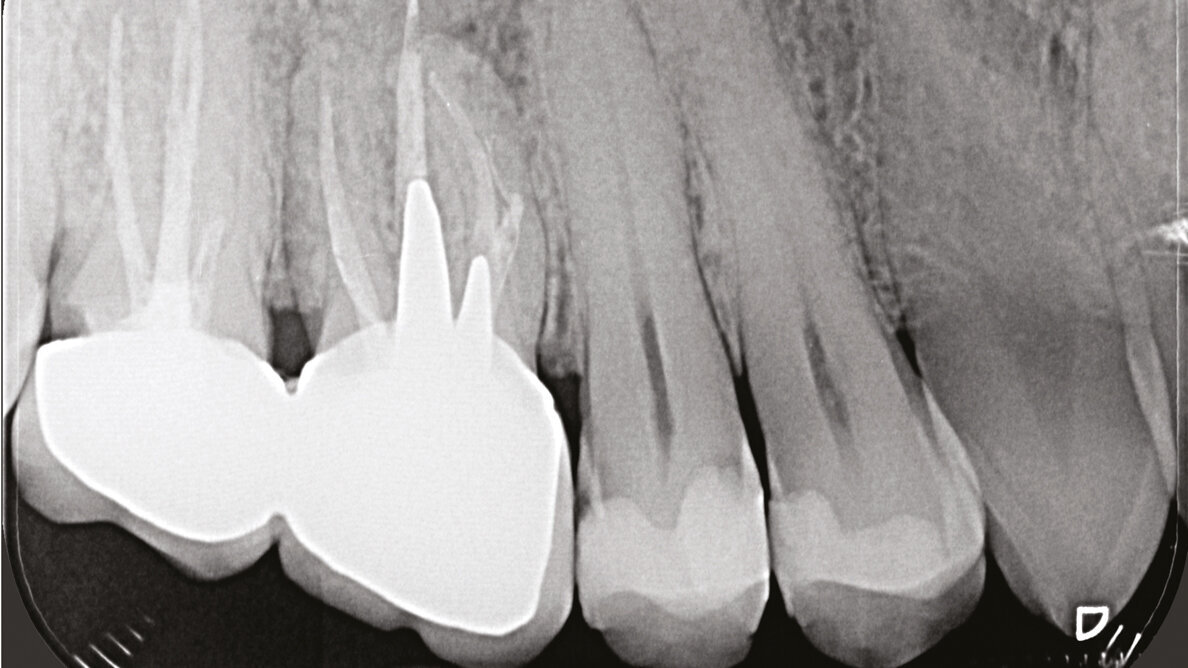

Fig. 1a - Il paziente è stato inviato per la terapia chirurgica della radice mesiovestibolare del primo molare superiore di destra.

Fig. 1b - Una radiografia presa con diversa angolazione sembra confermare che l’unica radice coinvolta nella lesione periapicale è la mesiovestibolare.

Fig. 2a - Radiografia preoperatoria del secondo molare superiore di sinistra. La paziente lamenta dolore alla masticazione su questo dente, trattato endodonticamente pochi mesi prima. La stessa viene indirizzata con la specifica richiesta di eseguire la terapia chirurgica e di non aprire una cavità d’accesso, allo scopo di non sciupare la “nuova” corona ceramica da poco cementata.

Fig. 2b - Una piccola lesione è evidente all’apice della radice mesiovestibolare.